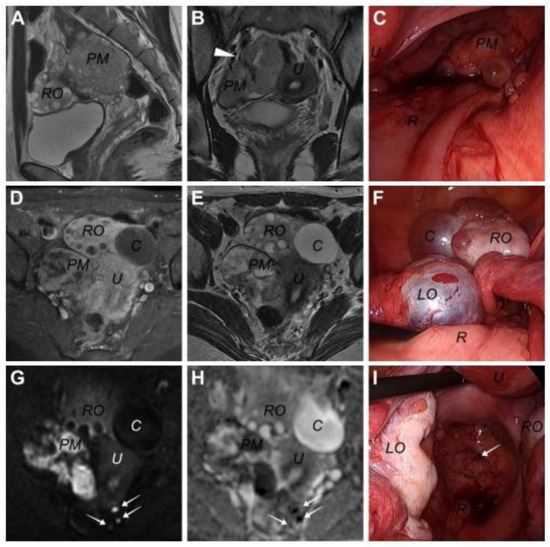

On 10 February 2023, a 31-year-old woman visited our institution with lower abdominal pain. The patient underwent laparoscopic unilateral ovarian cystectomy in another medical institution due to an unknown pathologic diagnosis approximately 4.5 years before the presentation. Whether surgical spillage occurred or not in this laparoscopic surgery was unclear. Computed tomography (CT) and subsequent magnetic resonance imaging (MRI) revealed a 6.5 × 4.0 cm multi-loculated cystic mass lesion arising from the right pelvic wall, along with a 4 cm sized cystic tumor in the right ovary (Figure 1). The pelvic mass was observed to be supplied by the right internal iliac artery in the coronary view of T2-weighted MRI (Figure 1B). Contrast-enhanced T1-weighted MRI revealed contrast enhancement throughout the pelvic mass, except for the internal cystic component (Figure 1D). The pelvic mass exhibited a high signal intensity (SI) on the diffusion-weighted MR image (b = 1000 s/mm2), and the apparent diffusion coefficient map showed a signal loss, indicating a highly cellular tumor (Figure 1G). Additionally, some lesions with similar SIs were observed in the rectal serosa, which were later confirmed as tumor seeding in laparoscopic exploration (Figure 1G,H). For this pelvic mass, a neurogenic tumor, such as a benign schwannoma, was suspected, whereas a benign cystic tumor and functional cyst were suspected in the right and left ovaries, respectively. No other abnormal findings, including ascites or lymphadenopathies, and the pancreas, were observed on MRI and CT. This study was approved by the Institutional Review Board of Kyungpook National University Hospital (KNUH 2023-06-015).

On 25 April 2023, the colorectal surgeon in our institution performed laparoscopic exploration. Intraoperatively, the surgeon detected seeding lesions on the rectal serosa and an isolated pelvic mass on the right side of the pelvic cavity. Moreover, the surgeon noted several small cystic or polypoid spherical mass lesions on the surfaces of both ovaries, fallopian tubes, and pelvic peritoneum (see Figure 1C, Figure 1F and Figure 1I, respectively). The mass was laparoscopically removed; subsequently, the surgeon called the gynecologic surgeon to examine the bilateral ovarian lesions. The capsules of the bilateral cystic lesions were resected and sent to a pathologist for frozen section analysis, which revealed the possibility of malignancy. Following permanent pathologic examination, both ovarian capsules and peritoneal lesions were diagnosed with solid pseudopapillary tumors. Following this diagnosis, whole-body positron emission tomography/CT was performed; however, no specific lesion in the pancreas or other distant organs was observed.

Figure 1. Images of pelvic magnetic resonance imaging and laparoscopic findings in a 31-year-old woman diagnosed with primary solid pseudopapillary neoplasm (SPN) in this case. (A) Sagittal T2-weight image, (B) coronary T2-weighted image, (C) pelvic mass in laparoscopy, (D) contrast-enhanced T1-weighted image, (E) transverse T2-weighted image, (F) both ovaries in laparoscopy, (G) diffusion-weighted image, (H) the ADC map, and (I) metastatic lesions of the peritoneum in laparoscopy. (PM: pelvic mass, RO: right ovary, U: uterus, R: rectum, C: right ovarian cystic lesion, LO: left ovary, arrowhead: right internal iliac artery supplying the pelvic mass, white arrows: metastatic lesions on rectal serosa or peritoneum).